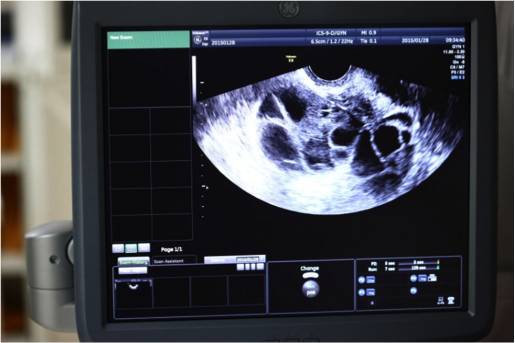

李媛:夫妇性生活正常,积极试孕,未避孕未孕一年称为不孕症(不育症)。90%的夫妇在一年内能正常怀孕,剩余的那一部分可能存在影响怀孕的疾病,需要就诊生殖中心或不孕不育门诊进行诊断和治疗。主要从女方卵巢功能、排卵情况、输卵管情况、子宫内膜情况、男方精液常规等方面检查,先找到不孕原因再治疗。

网友:去年7月开始连着促排卵三个月都正常。后来b超显示没有多囊卵巢了,内分泌六项也都正常。但是现在又有将近三个月没来月经了,接着该怎么办呢?

李媛:如果排卵好,精子好,那就查一下输卵管,做一个输卵管造影检查,月经干净后2-7天查,从来月经开始不同房。可以再做个超声看看子宫内膜情况。